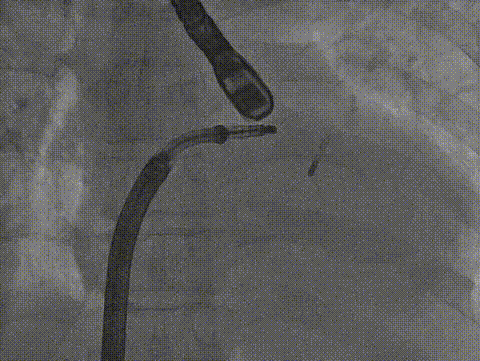

术中影像

房间隔穿刺

导引鞘置入左房

长宽夹打弯至瓣上

房间隔穿刺高度

导引鞘置入